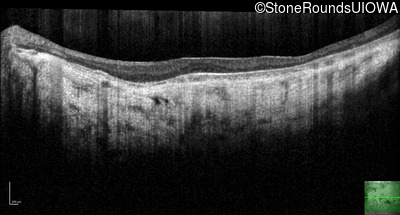

Optical Coherence Tomography - Left - 20/32 -2

Exemplar / OCT Stack

OCT Stack